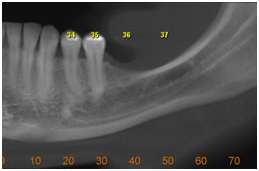

• Avaliar o grau de reabsorção radicular de dentes adjacentes a caninos retidos

Reabsorção radicular adjacente a dentes retidos Reabsorção radicular adjacente a dentes retidos